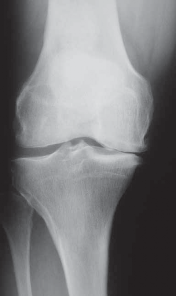

4. Further radiographic evaluation includes a mechanical axis view (hip-knee-ankle). This view makes it possible to determine initial varus and valgus alignment of the bilateral lower extremities and the overall mechanical axis, and to

template correction angles for the opening wedge HTO (

FIG 2C

).

FIG 2 • A. AP radiograph of the right knee showing significant narrowing of the medial joint space with flattening of the medial femoral condyle and osteo-phyte formation. B. PA 45-degree flexed view (ie, Rosenberg view) of the same knee is obtained to show a different tangential view of the condyles. In this view, the patient has cartilage space remaining, but the medial compartment is narrowed. The numbers written in the condyles represent millimeters of joint space. C. Mechanical axis view of the bilateral lower extremities shows severe bilateral varus deformities of the lower extremity. Although the picture is underpenetrated toward the femoral heads, the steps for obtaining the mechanical axis are as follows: (1) Mark the center of the femoral head. (2) Mark the center of the ankle. (3) Draw a straight line between them (ie, the most medial line on the illustration). If the line is medial to the center of

the knee, then the patient is in varus. If it is lateral,

the patient is in valgus. In this case, the patient is in severe varus.